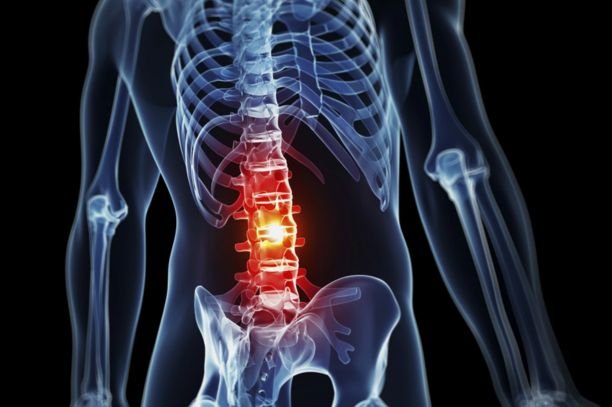

Back Pain

Comprehensive Back Pain Treatment by Dr. Nitish Agrawal – Best Spine Surgeon in Pune

Back Pain is one of the most common spine-related problems affecting people of all age groups. It can range from mild discomfort to severe, disabling pain that interferes with daily activities and quality of life. Back pain may be caused by poor posture, muscle strain, degenerative spine conditions, injury, disc problems, or nerve compression.

Common Causes of Back Pain

Back pain can develop due to multiple reasons, including:

Symptoms of Back Pain

Symptoms may vary depending on the underlying cause and may include: